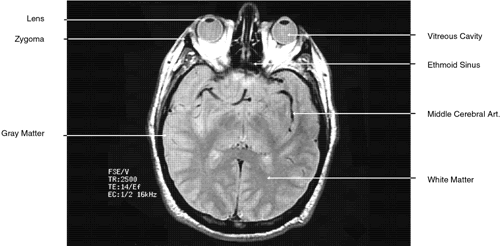

Fig. 7. Axial T1-weighted magnetic resonance imaging through midglobe.

Fig. 8. Axial proton-density magnetic resonance imaging through midglobe.

T2-weighted images can be produced at the same time as proton density images. In this case both the TR and TE are prolonged. By allowing all tissues to relax maximally, the most intense signal will be produced by the tissue with the longest T2 (that is, the tissue that remains coherent the longest). A particular tissue's T2, which typically ranges between 25 and 150 msec, is usually much shorter than its T1. To obtain a T2-weighted image, both the TR (>2,000 msec) and the TE (50 to 150 msec) are long (Fig. 9). In such cases, vitreous and cerebrospinal fluid give the most intense images and fat, white and gray matter, bone, and air give the least intense images.

Fig. 9. Axial T1-weighted magnetic resonance imaging through midglobe.

During MRI, the T1 and T2 differences between various tissues can be weighted to enhance the MR image produced. Essentially, this process increases the contrast between adjacent tissue structures and improves their visualization. This is ac-complished by varying within a particular pulse sequence either the repetition time (TR) betweenapplied radiofrequency pulses and the echo time(TE), or the time between the applied pulse andthe detection of the produced signal. A short TRfavors tissues with a short T1, such as fat. For exam-ple, with a TR of 300 msec, tissues will be enhanced in the following order: fat > white matter > gray matter > uvea > aqueous > vitreous, optic nerve, muscle > cortical bone. The reason for the intense response of fat is that with a short T1 it can almost completely recover its resting state between pulses. This enables it to respond again to the next pulse. Generally, T1-weighted images have a pulse sequence with a TR of 200 to 1,000 msec as well as a short TE (20 to 25 msec) (Fig. 7). The longer a particular tissue's T1, the less it can respond to the next pulse, because fewer of its protons have returned to a resting state. Therefore, its MR image is less intense. Lengthening the TR will allow more protons time to relax until the signal produced no longer depends on a tissue's T1. The image produced when the TR is long (2,000 to 2,500 msec) is “proton density”-weighted (Fig. 8). When this is the case, tissues with the highest proton density (e.g., gray matter and old hemorrhage) produce the most intense signal. In both T1- and proton density-weighted images, the TE is short (20 to 25 msec). The clearest anatomical delineation between tissues is provided by highly T1-weighted images with TR values between 300 and 500 msec.25,26